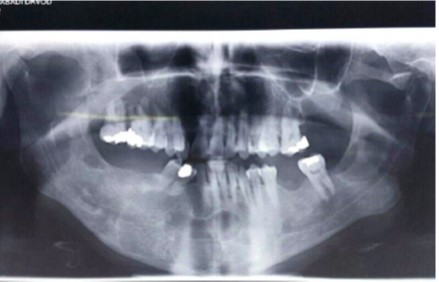

The panoramic radiographs showed seven cysts in the mandible and maxilla. The patient was then referred to the surgical unit of the School of Dentistry. A CT scan was performed in order to better examine the patient and the images obtained revealed multiple extended cysts in the posterior and anterior mandible and maxilla with no swelling. The CT scan and panoramic radiographs showed multiple radiolucencies with well-demarcated borders, cortical margins and different sizes (Figure 3 and Figure 4). The interpretation of the radiographic images diagnosed the patient with radicular cysts and odontogenic keratocysts. The clinical examination of the patient revealed no systemic diseases or symptoms in the skin and the involved areas. The chest and skull radiographs also showed no symptoms.

Figure 3.The panoramic radiograph showing multiple cysts in the maxilla and mandible